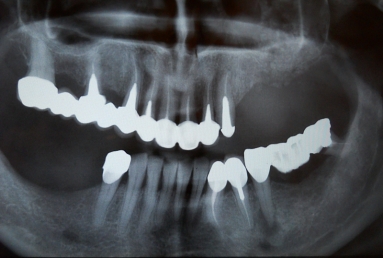

Initial situation: The patient needs dental implants on the left side of the maxillary jaw in order to have a fixed prosthetic restoration. But the bone is insufficient vertically and laterally, because the extractions were made a long time ago, which caused the extreme bone resorption and the vertical migration of the sinus floor.

Final situation: an external sinus lifting procedure was performed. The sinus membrane was lifted off the sinus walls and new bone was applied in the vertical space created ( Bio Oss- switzerland- bovine origin). After 6 months, while the new bone is integrated in the maxillary bone of the patient, dental implants can be applied. the case is still during treatment.